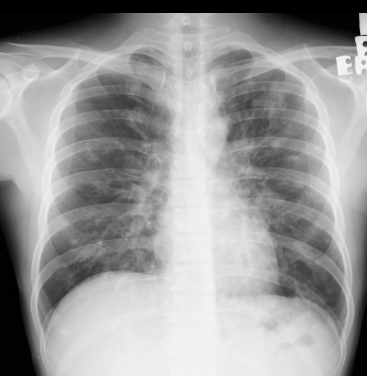

Général

- Patients HIV <200 CD4++ ou Patients Transplantés ++

- Condensations nodulaires mal définies, “en flamme”

- Péribronchovasculaire

- DD: Lymphome lié au SIDA (2e plus fréquent)

kaoposi aids sida vih hiv lung poumon poumons thorax thoracique sarcoma